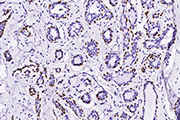

KRT19 antibody (Cat#: 100306-MM08)

Immunochemical staining of human KRT19 in human thyroid cancer

Immunochemical staining of human KRT19 in human thyroid cancer. Image Credit: Sino Biological Inc.